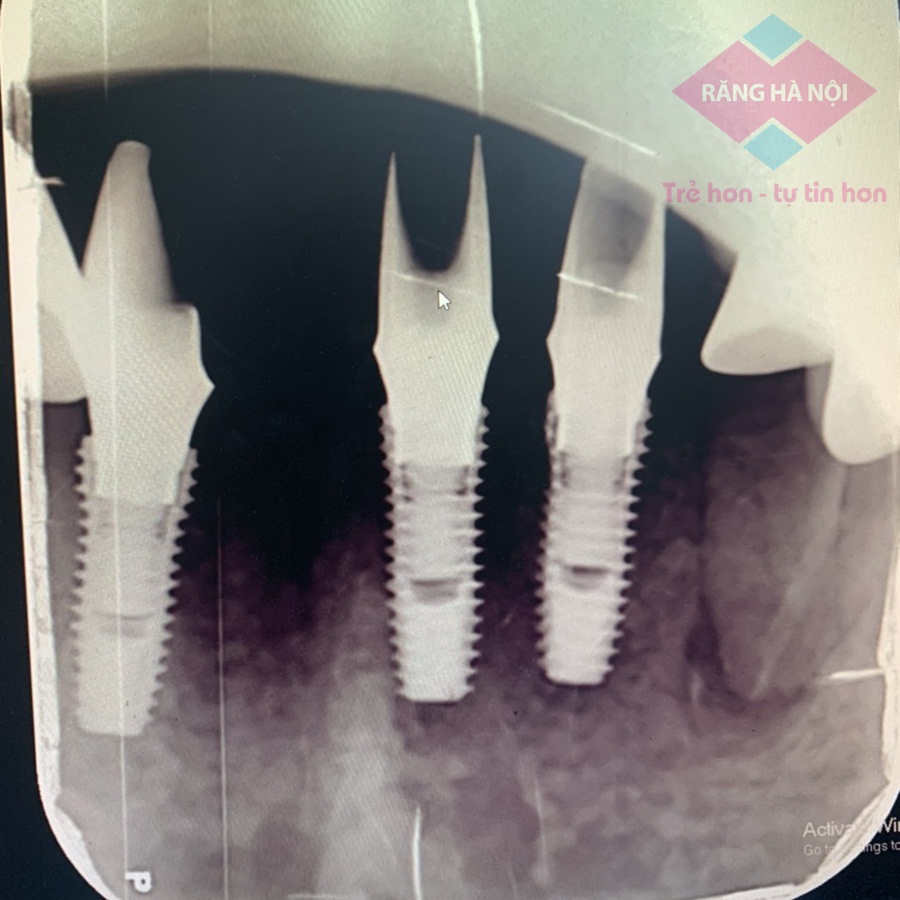

Một chiếc răng Implant có cấu tạo gồm 3 phần: trụ Implant, kết nối Abutment và mão răng sứ. Phần trụ Implant sẽ được cấy vào trong xương hàm, thay thế cho phần chân răng thật đã mất, phần trụ sẽ nâng đỡ mão răng sứ phía trên thông qua kết nối Abutment.

Trụ răng Implant sau khi cấy ghép

Tùy vào những vị trí cấy ghép khác nhau sẽ có những loại trụ Implant với kích thước và chiều dài khác nhau. Bác sĩ sẽ lựa chọn loại trụ phù hợp nhất cho bệnh nhân dựa trên kết quả chụp phim CT 3D. Đảm bảo trụ Implant được cấy vào xương hàm sẽ không quá sâu, để không gây ảnh hưởng đến các mô mềm và hệ thần kinh, cũng không quá nông, nếu không sẽ thiếu chắc chắn.